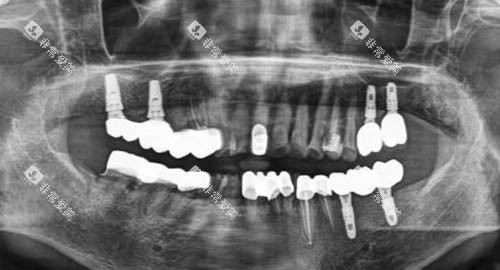

在种植牙方面,医院采用德国卡瓦智能化导航系统,支持即刻种植、ALL - ON - 4/6全口修复,误差控制在0.1mm,单颗种植周期缩短至1小时,大大提高了种植效率和精密度。

同时,医院还配备了智能化X光机、种植导航系统等实力设备,从设备上确保了诊疗的可靠性。